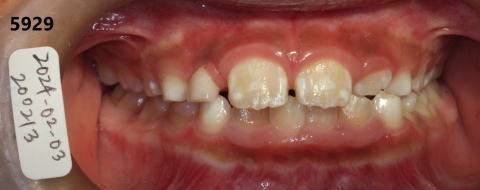

2024年02月03日

咬合をあげてから

約1年3ヶ月後。